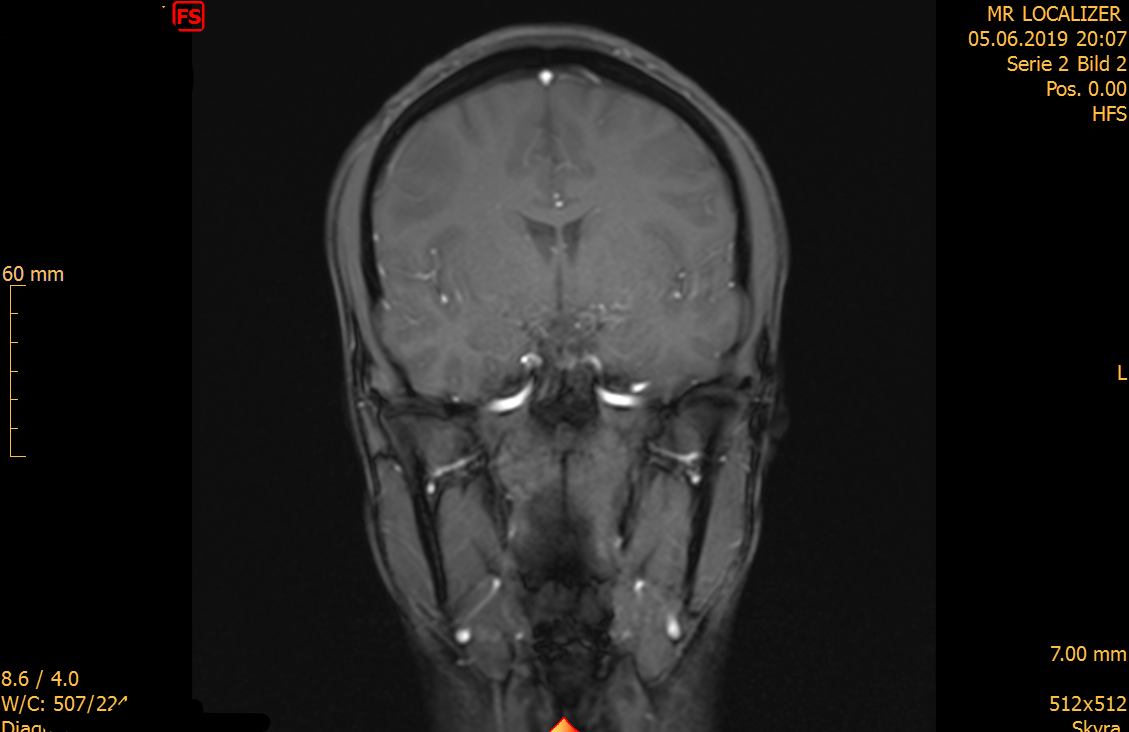

Weiße Flecken Im Gehirn Bei Mrt . t2_sag100001 MRT des Kopfes in sagittaler Ebene DocCheck MS-typische Veränderungen ("weiße Flecken") stellen rundlich-ovale Herde dar, die vor allem um die Hirnkammern herum (periventrikulär) angeordnet sind, aber auch den Übergang zwischen Hirnstamm und Kleinhirn und das obere Rückenmark betreffen können. bei Zysten) oder Vernarbungen im Bereich des Gehirns hindeuten.

Auffällig viele weiße Flecken im Gehirn DNP Die Neurologie & Psychiatrie Was sind weiße Flecken? Flecken auf einem Gehirn-MRT werden durch Veränderungen des Wassergehalts und der Flüssigkeitsbewegung verursacht, die im Hirngewebe auftreten, wenn die Gehirnzellen entzündet oder geschädigt sind. Ein diffiziles Thema sind weiße Flecken im Gehirn Während schon die Termini vielfältig sind, gestaltet sich die Differentialdiagnose noch umfangreicher

Source: newsancexgi.pages.dev Schädel MRT Localizer Was sind das für weiße Stellen? , Was sind weiße Flecken im MRT? Von besonderer Bedeutung ist die Kernspintomographie (MRT) It affects millions of individuals worldwide, significantly impacting their quality of life

Source: ocharterjet.pages.dev Weisse Flecken Auf Mrt Bild Wirbelsaule Beste Ideen Bilder , Was bedeuten weiße Flecken im MRT? Läsionen der weißen Substanz, die in Magnetresonanztomographie-Scans (MRT) als Hyperintensitäten sichtbar werden, weisen auf eine abnormale Myelinisierung im Gehirn hin und dienen als Marker für die Erkrankung der kleinen Gefäße Ein diffiziles Thema sind weiße Flecken im Gehirn